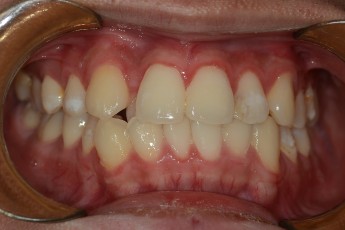

BEFORE & AFTER

- 덧니교정